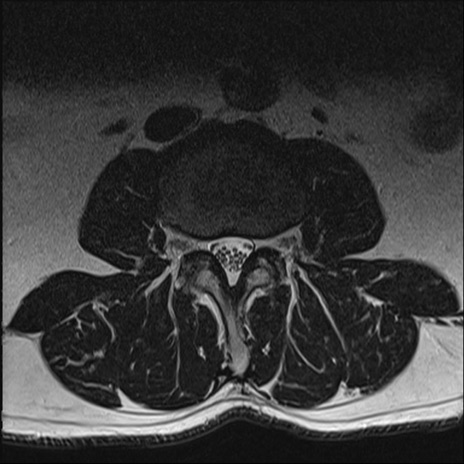

【整形】TIPS症例2 腰椎MRI T2WI(横断像)

【症例】70歳代男性

【主訴】左下肢痛

【現病歴】2週間前くらいから腰痛、左下肢痛あり。左臀部から大腿、下腿外側のしびれが常時ある。歩行とともに同部位の痛みあり。

【身体所見】Lasegue70-/60+、Bragard-/±、PTR ±/±、ATR -/-、IP 5/5、TA 5/4、TS 5/5、EHL 右第1足趾なし/3、FHL 5/5、hypersthesia(-)、足背動脈触知良好

異常所見と診断は?